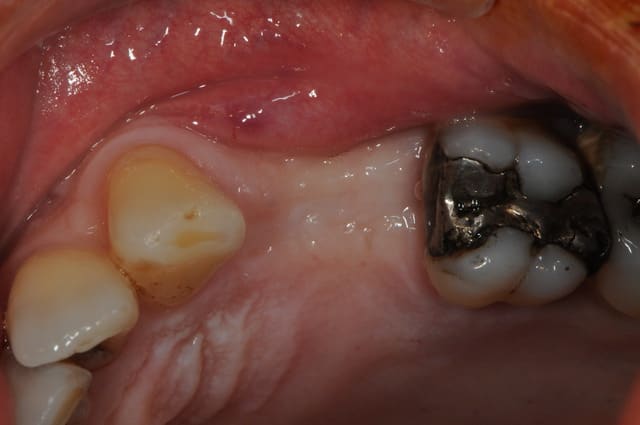

tiens voici des photos de ce matin...

patient avec kyste +++ aux apex et fenestration

je n'implante pas

je comble au Graftec

je met une membrane

je referme

8 mois après,

je vais implanter

comme je suis curieux, j'ouvre large et je regarde;

c'est décevant,le volume est là mais l'os n'est pas génial.

voilà pour les photos...

pendant que je forais, et le patient le sentait également, je sentais et entendais les particules de graftec.

en plus au bout de 8 mois j'aurai espéré trouver quelque chose de mieux non ?